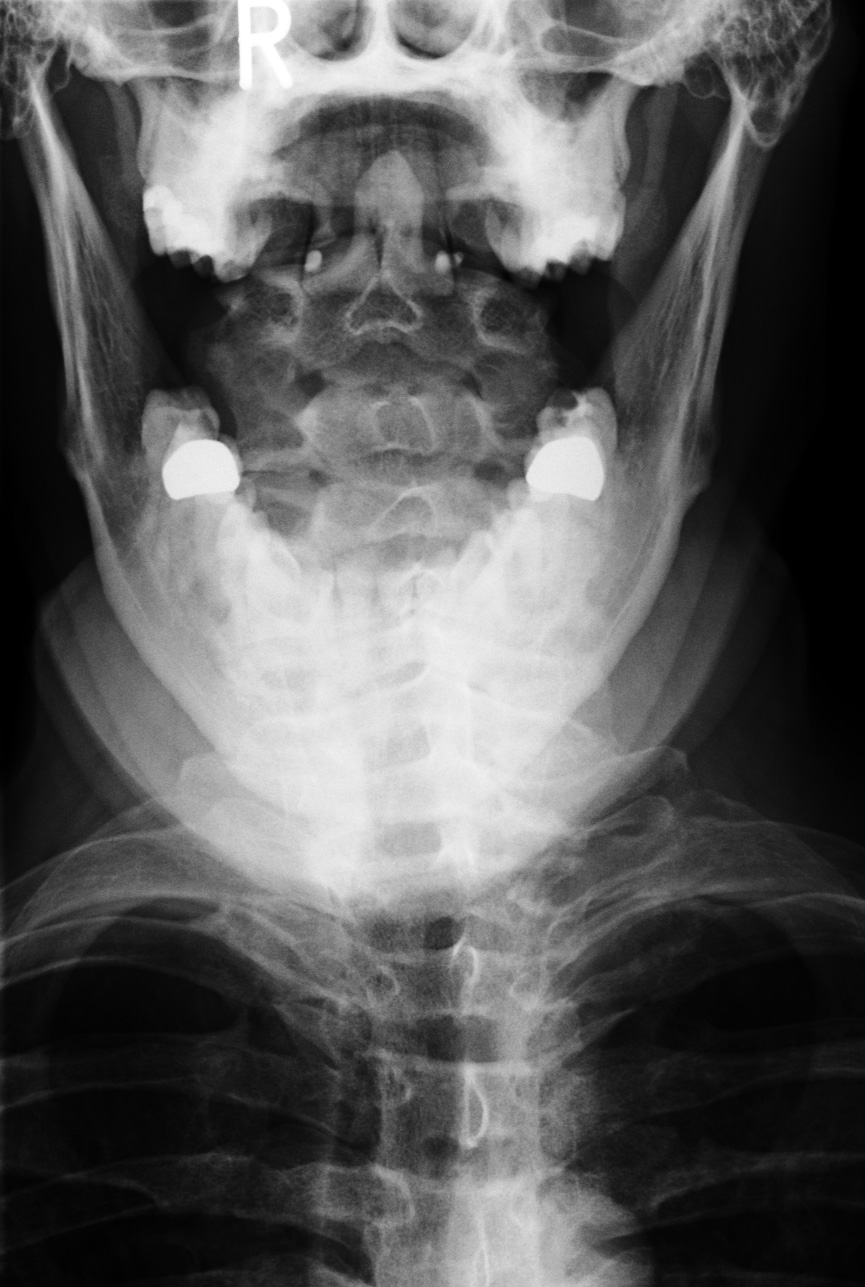

Bechterew